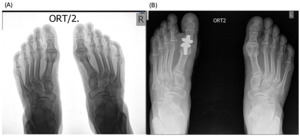

._patient_b__immediate_postoperative_radiograph_(b).png)

._patient_b__6-month_follow-up_radiograph_(b).png)